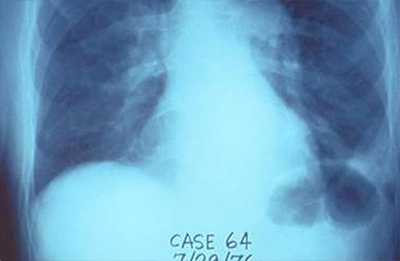

People with Legionnaires’ disease have pneumonia (lung infection) since the Legionella bacteria grow and thrive in the lungs. Pneumonia is confirmed either by chest x-ray or physical exam.